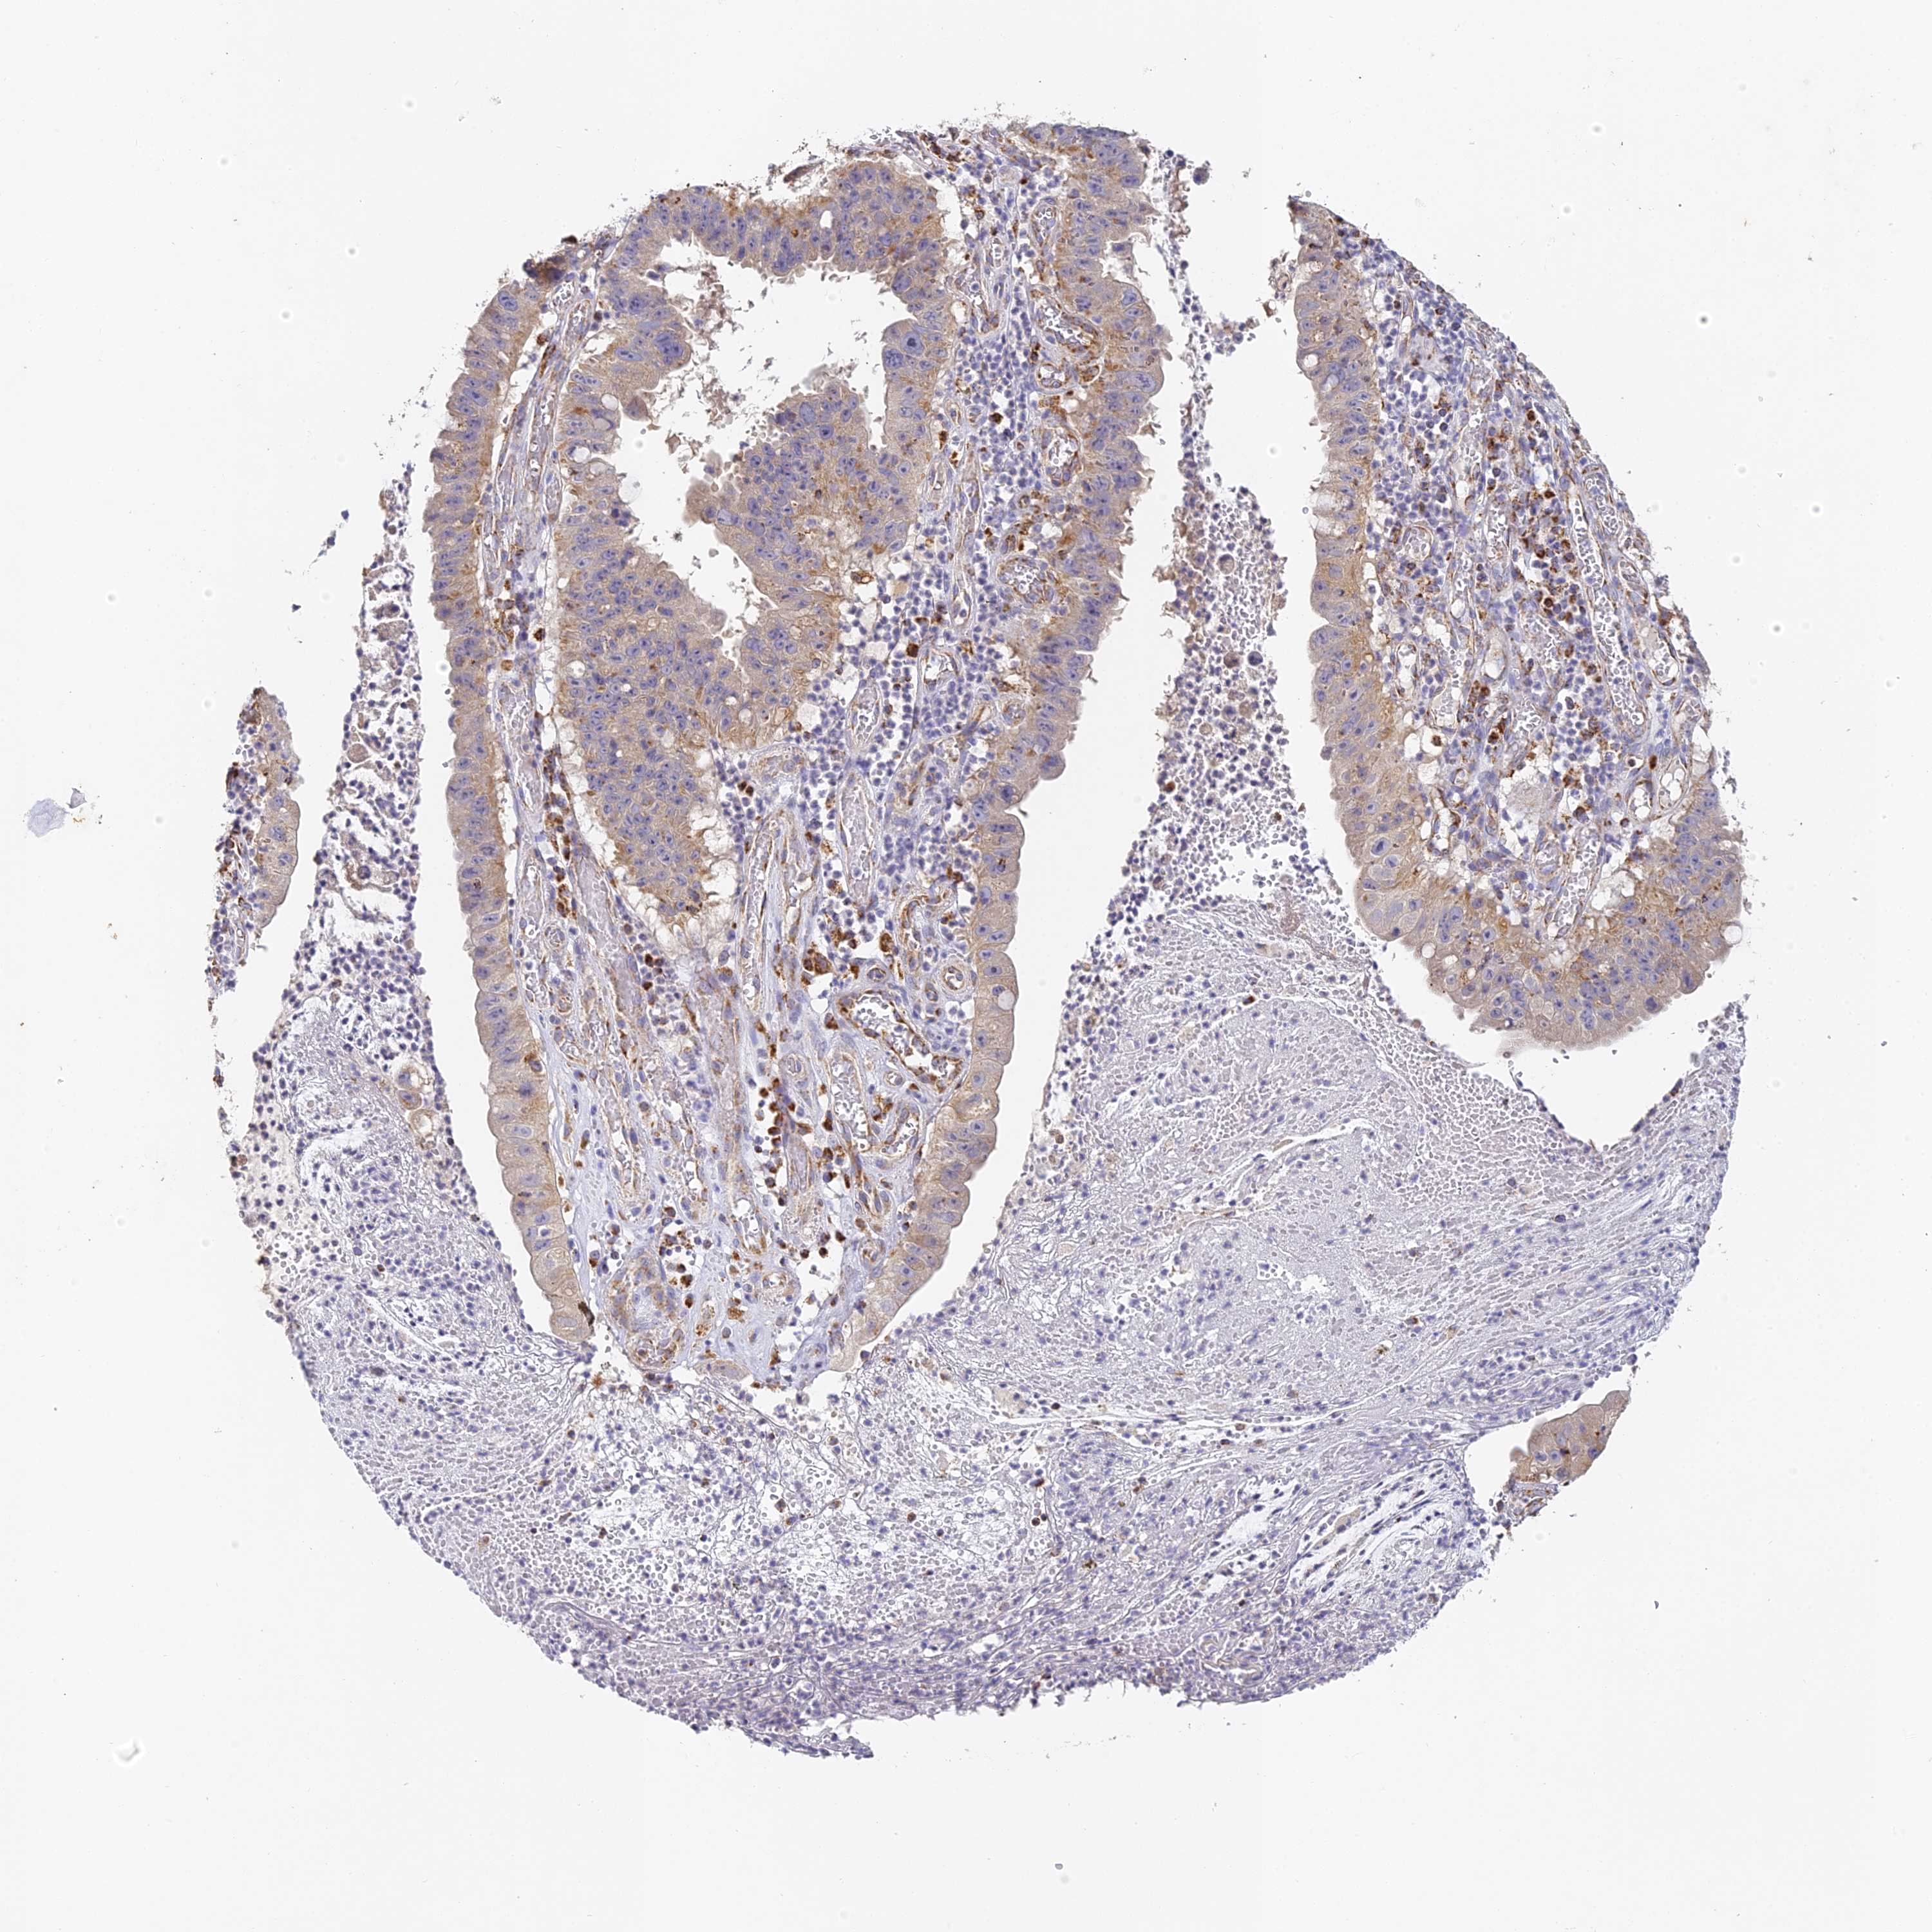

STOMACH CANCER - Protein expressioni

A mouse-over function shows sample information and annotation data. Click on an image to view it in a full screen mode. Samples can be filtered based on level of antibody staining by selecting one or several of the following categories: high, medium, low and not detected. The assay and annotation is described here.

Note that samples used for immunohistochemistry by the Human Protein Atlas do not correspond to samples in the TCGA dataset.

Antibody stainingi

Antibody staining in the annotated cell types in the current human tissue is reported as not detected, low, medium, or high, based on conventional immunohistochemistry profiling in selected tissues. This score is based on the combination of the staining intensity and fraction of stained cells.

Each image is clickable and will lead to virtual microscopy that enables deeper exploration of all samples and also displays staining intensity scores, fraction scores and subcellular localization as well as patient and tissue information for each sample.

Antibody HPA039558

Antibody HPA049033

Staining

High

Medium

Low

Not detected

Intensity

Strong

Moderate

Weak

Negative

Quantity

>75%

75%-25%

<25%

None

Location

Nuclear

Cytoplasmic/membranous

Cytoplasmic/membranous,nuclear

Adenocarcinoma, NOS

Adenocarcinoma, High grade